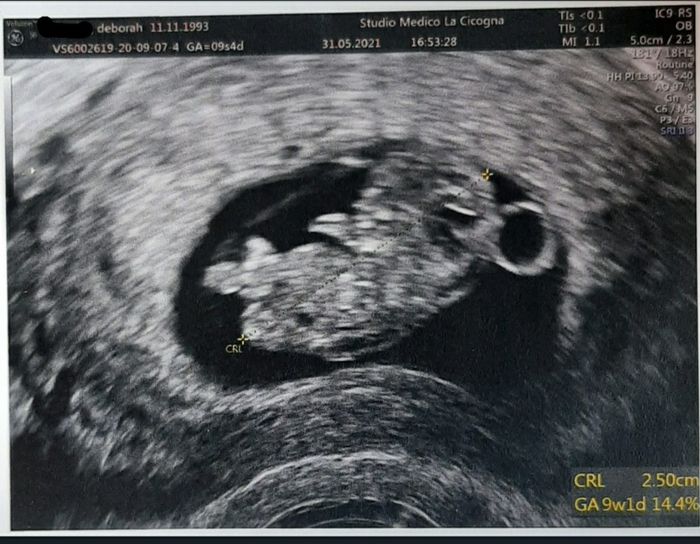

Future mamme di Gennaio 2022

Da Deborah , Il 3 Giugno 2021 alle 11:11

Ciao apro questo topic per le future mamme del nuovo anno ☺️ieri ho scoperto di aspettare il mio secondo bimbo, ne ho già uno di 2 anni.Spero che il gruppo si popolerà...